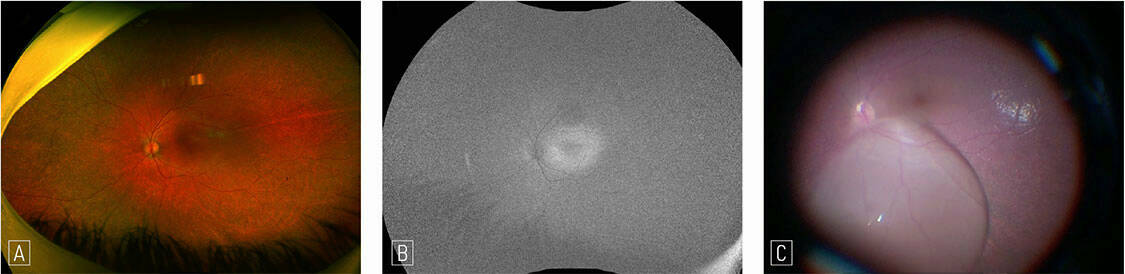

Figure 2. Patiente de 26 ans présentant une baisse d’acuité visuelle avec un décollement séreux rétinien hémorragique visible à l’OCT (A, tête de flèche). Les temps tardifs de l’angiographie à la fluorescéine ne montrent aucune diffusion (B) et la rupture de la membrane de Bruch est hypofluorescente sur le temps tardif de l’angiographie au vert d’indocyanine (C). L’OCT-A segmentée sur la rétine externe ne montre aucun signal vasculaire (D).